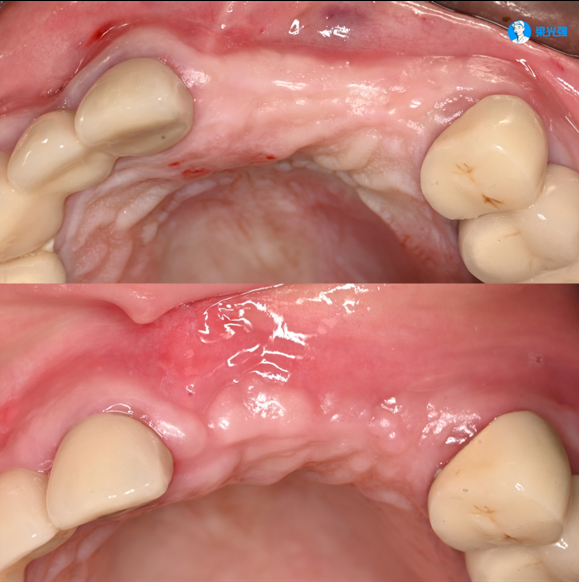

病例展示一

微信图片_2025-07-15_102943_896.jpg

病例展示二